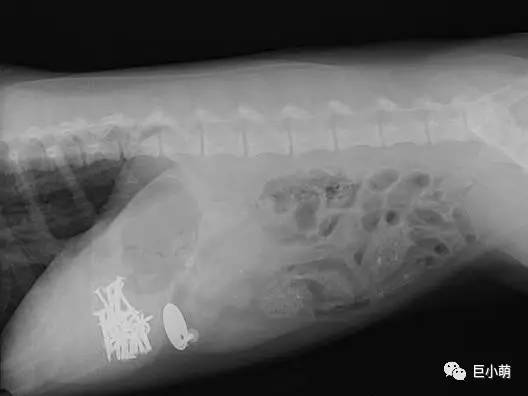

▲这堆钉子……你是刚逛完宜家吗?

异物堵住胃肠道,尖锐的物品(别针、缝衣针、小型玩具、超硬的骨头等)扎伤胃肠道;

如果这些异物和呕吐物、粪便一起排出的话也没问题,但如果异物排出不彻底而堵塞肠胃,症状就会逐渐恶化,最后可能会发展成为肠梗阻危及生命。